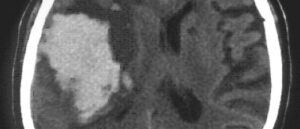

Гемангиома сосудов мозга

Гемангиома или кавернозная ангиома, кавернома — доброкачественное новообразование из клеток сосудов, которые расположены в центральной нервной системе, т. е. в мозгу. Это редкое заболевание и встречается у 0,4% людей. Гемангиома сосудов мозга не столь явно протекает (в 25% случаев асимптоматична) и не перерождается в злокачественное образование, однако, забывать о возможных последствиях не стоит, ведь некоторые …